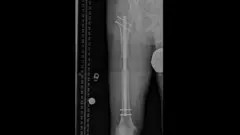

Me operé para alargar mis piernas y todo salió terriblemente mal

"Antes de operarme medía 1,63 m y ahora 1,70 m": el doloroso sacrificio de quienes se someten a una cirugía de elongación ósea